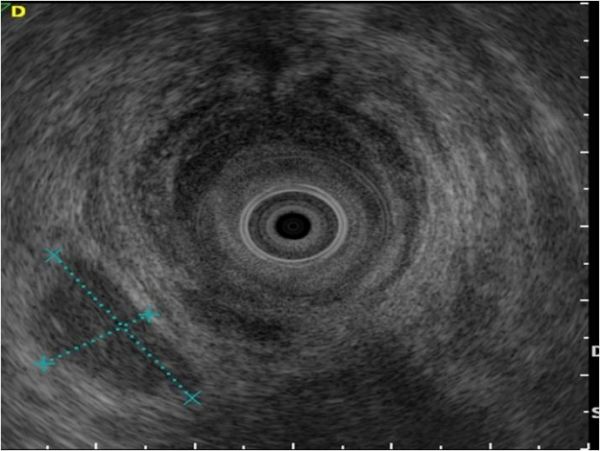

Die untere Endosonographie (EUS=Endo-Ultraschall) ist eine endoskopische Methode, die erlaubt, den Darmausgang bzw. Enddarm gleichzeitig zu spiegeln und mittels Ultraschall zu untersuchen. Sie ist die Methode der Wahl, um Enddarm- (Rektumkarzinom) oder Afterkrebs (Analkarzinom) abzuklären, bevor die korrekte Therapie eingeleitet werden kann. Die Methode wird auch zur Überwachung nach erfolgreicher Operation und/oder Chemotherapie bei diesen Krankheiten benötigt.

Bei Fisteln und Schliessmuskelschwächen des Afters (Inkontinenz) wird die Untersuchung direkt mit einer Endosonographie- (Ultraschall) Sonde ohne gleichzeitige Spiegelung durchgeführt.

Das knapp 1cm dicke Endoskop enthält an der Spitze neben einem Videochip einen kleinen Ultraschallkopf und wird durch den After eingeführt. In der Regel ist eine Darmreinigung wie bei der Dickdarmspiegelung zur Vorbereitung nötig. Die schmerzlose Untersuchung kann beim wachen Patienten durchgeführt werden.